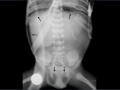

Figura 2- Na radiografia efetuada com raios horizontais as imagens nodulares apresentam níveis hidroaéreos, sendo compatíveis com abcessos pulmonares. Abaixo da hemicúpula diafragmática esquerda observa-se a bolha gástrica distendida (achado frequente em recém-nascidos).